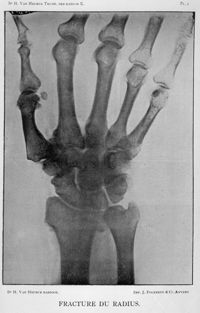

ImageFracture du radius